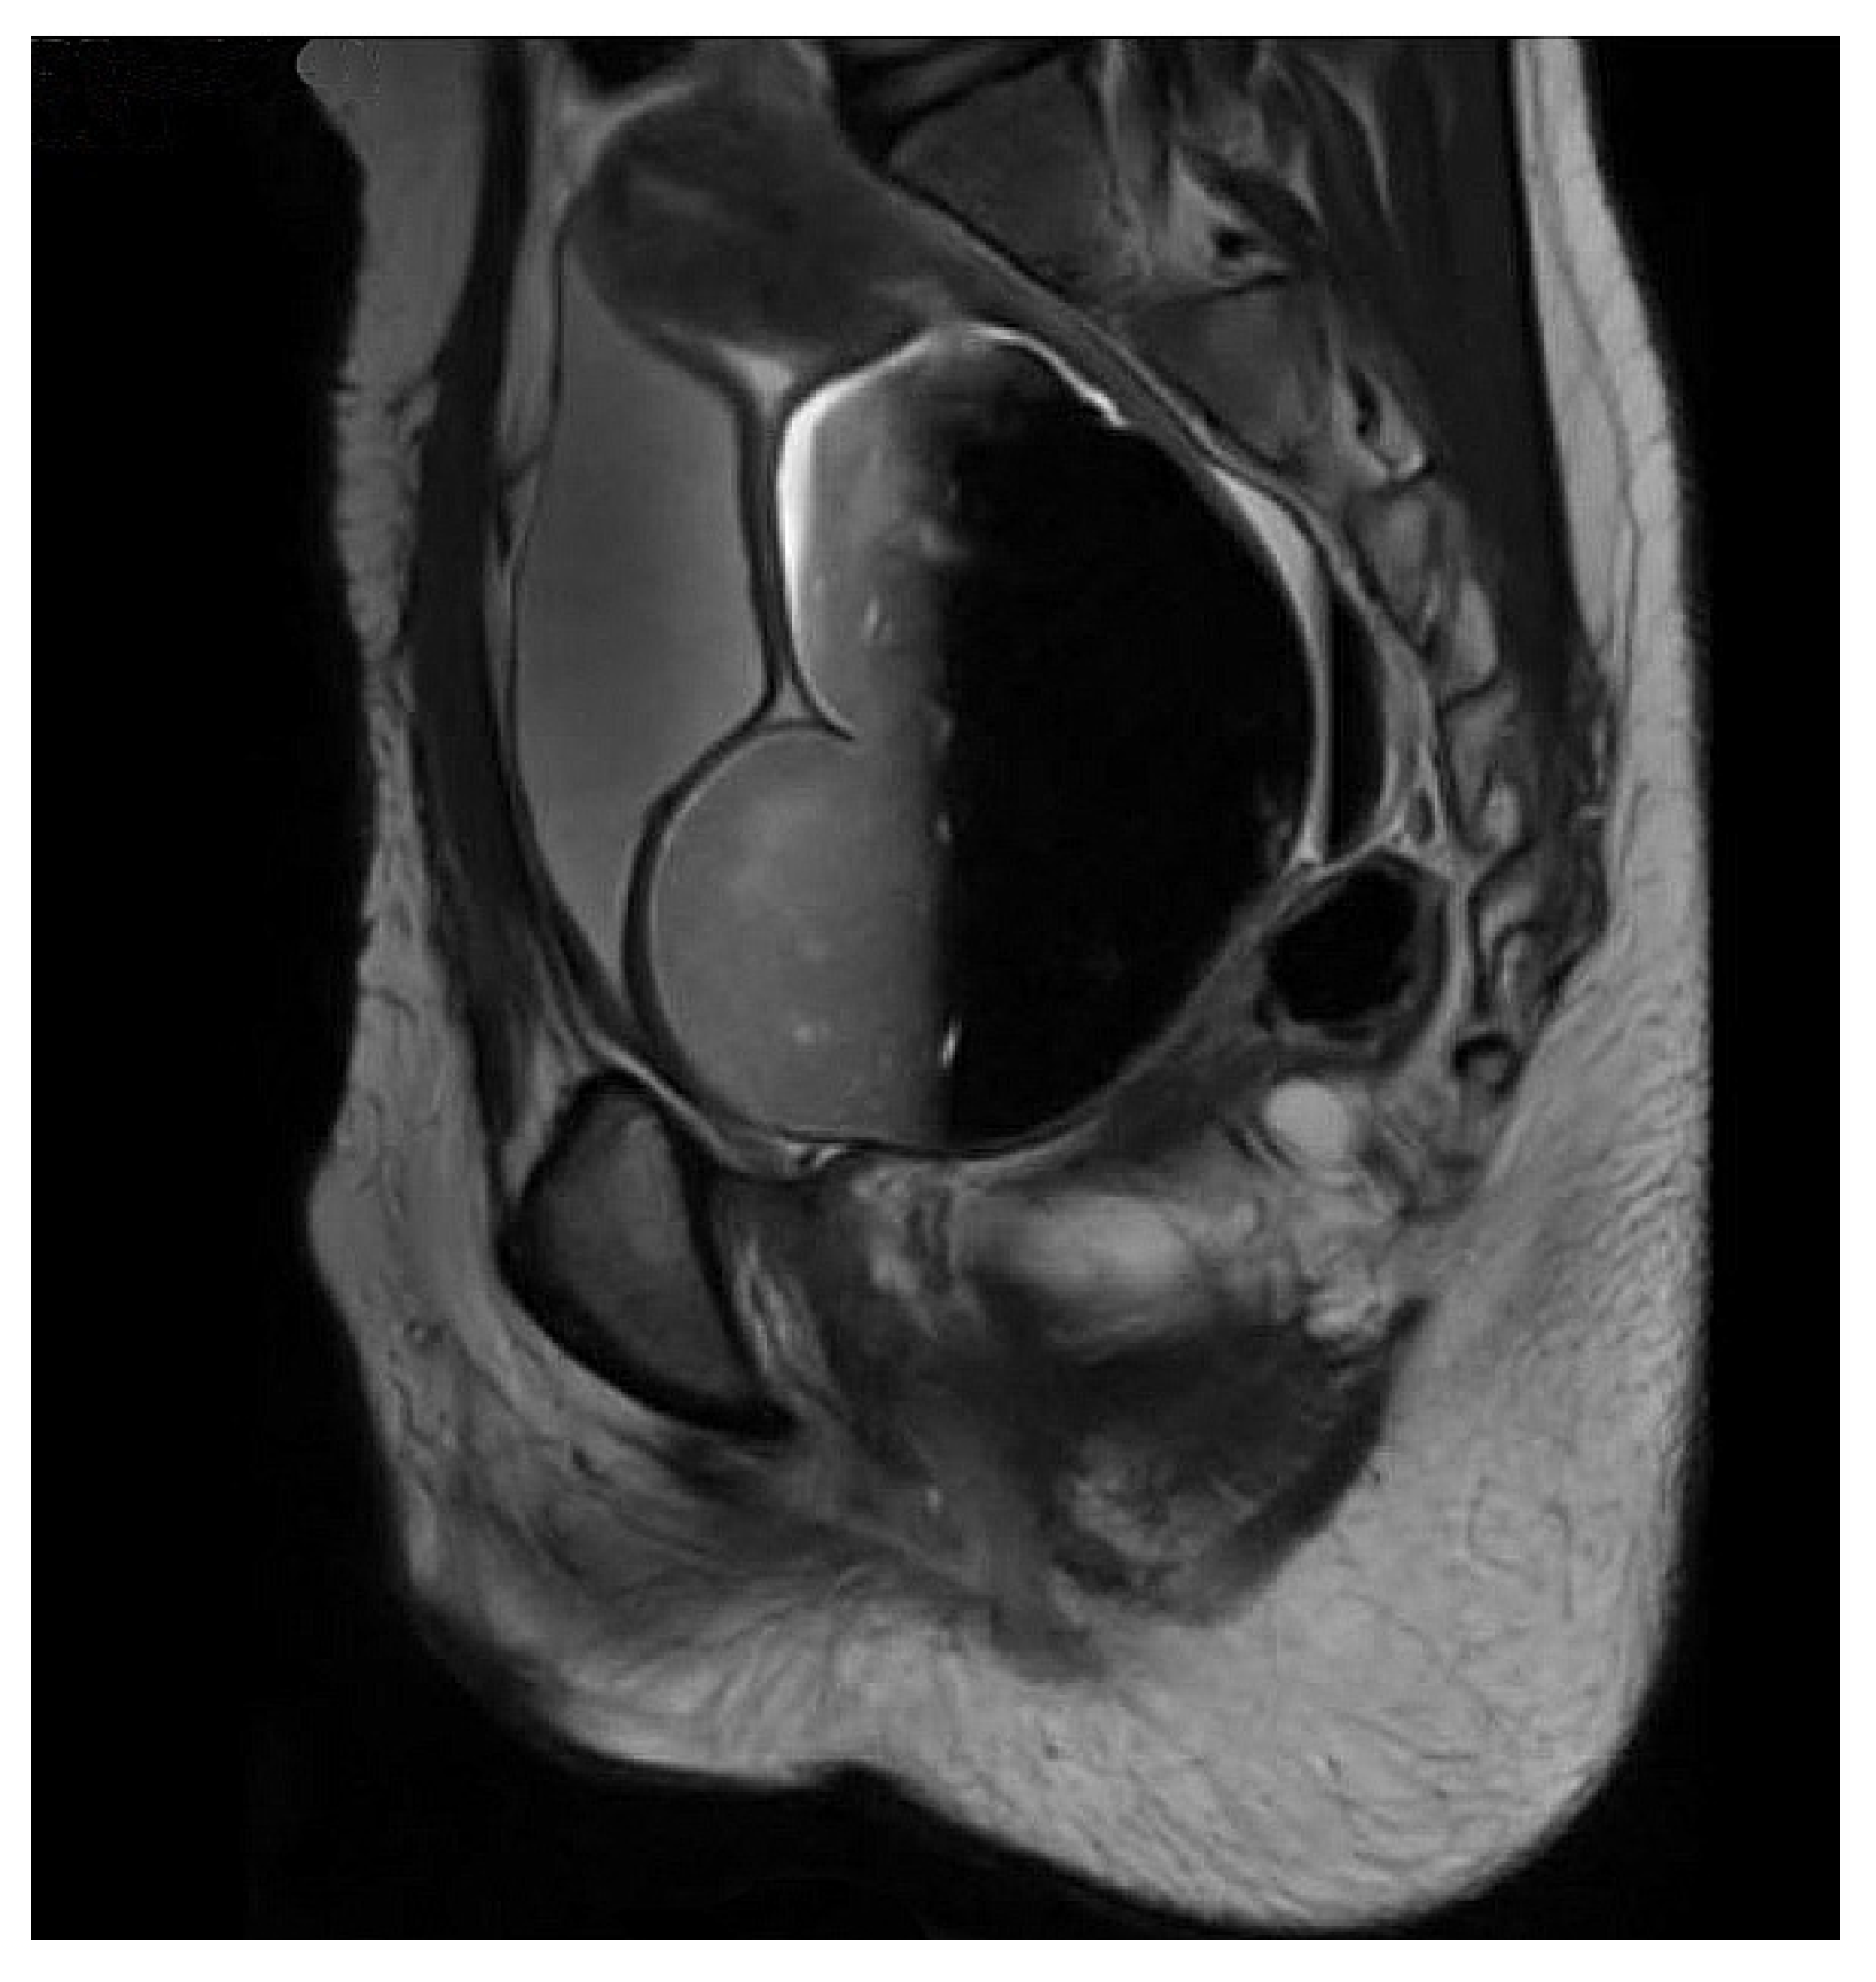

2. Materials and Methods

2.1. Approach

2.2. Transection at Bladder Neck

2.3. Transection at Proximal Urethra

2.4. Transection at Mid Urethra